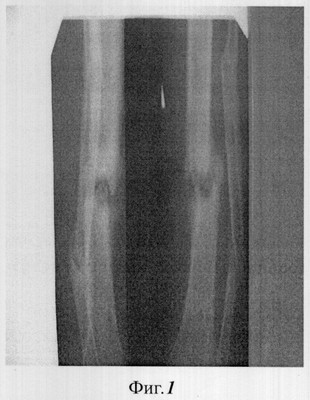

Фиг.1 – рентгенограмма ложного сустава до лечения;

Пример 1. Больной С. 21 года (история болезни №2816), инвалид 2 группы. Травму костей голени получил при выполнении служебного долга. В течение 2 лет перенес 4 операции. Сформировался дефект большеберцовой кости в форме ложного сустава (фиг.1). В зоне дефекта-псевдоартроза мягкие ткани рубцово-изменены.